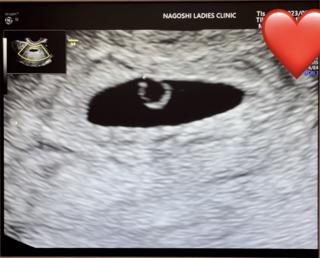

5w5dで2ミリの赤ちゃんに会えました。 心拍もピコピコと確認ができて感動。 次は1週間後なので今より大きく元気に成長していますように‼︎ 週数は6w1dに修正されました(◡̈)